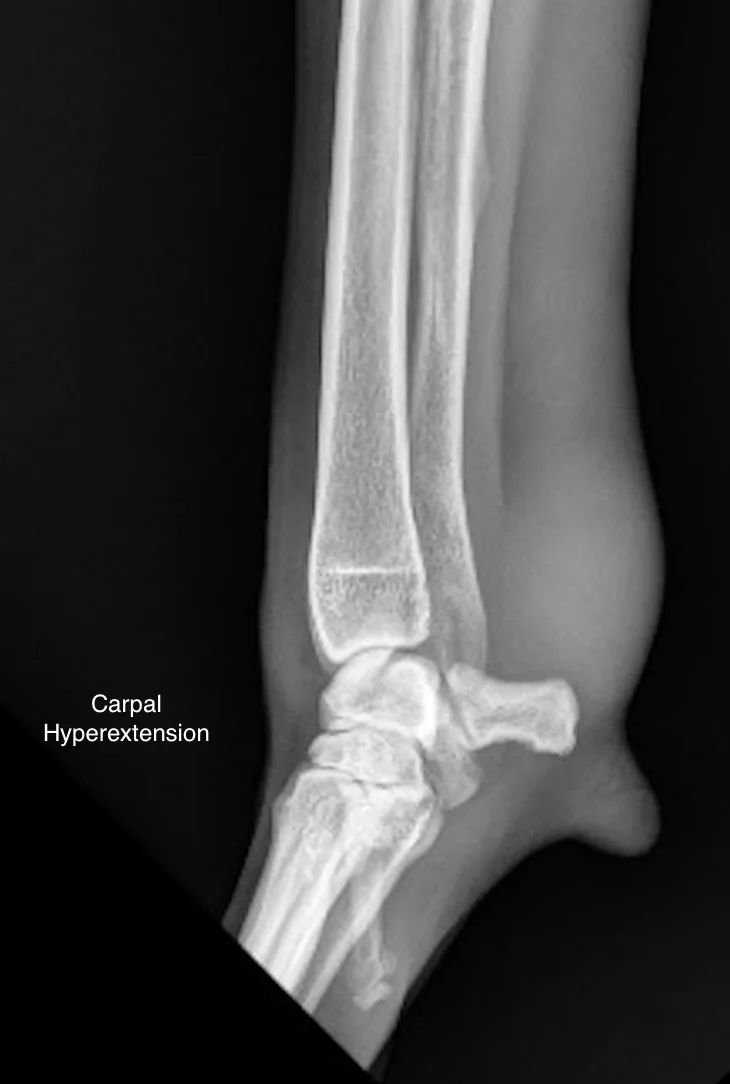

Lateral and craniocaudal radiographs of the left antebrachium did not reveal any fractures (Figure 2). A stressed, hyperextended lateral radiograph of the antebrachium to assess for palmar carpal stability was also normal.7

Lateral (A) and craniocaudal (B) radiographs of the left antebrachium. Thickening of the flexor carpi ulnaris tendon on the caudal aspect of the distal antebrachium is present (arrows). Hyperextended, stressed lateral radiograph of the carpus (C) does not show evidence of palmar ligament instability.